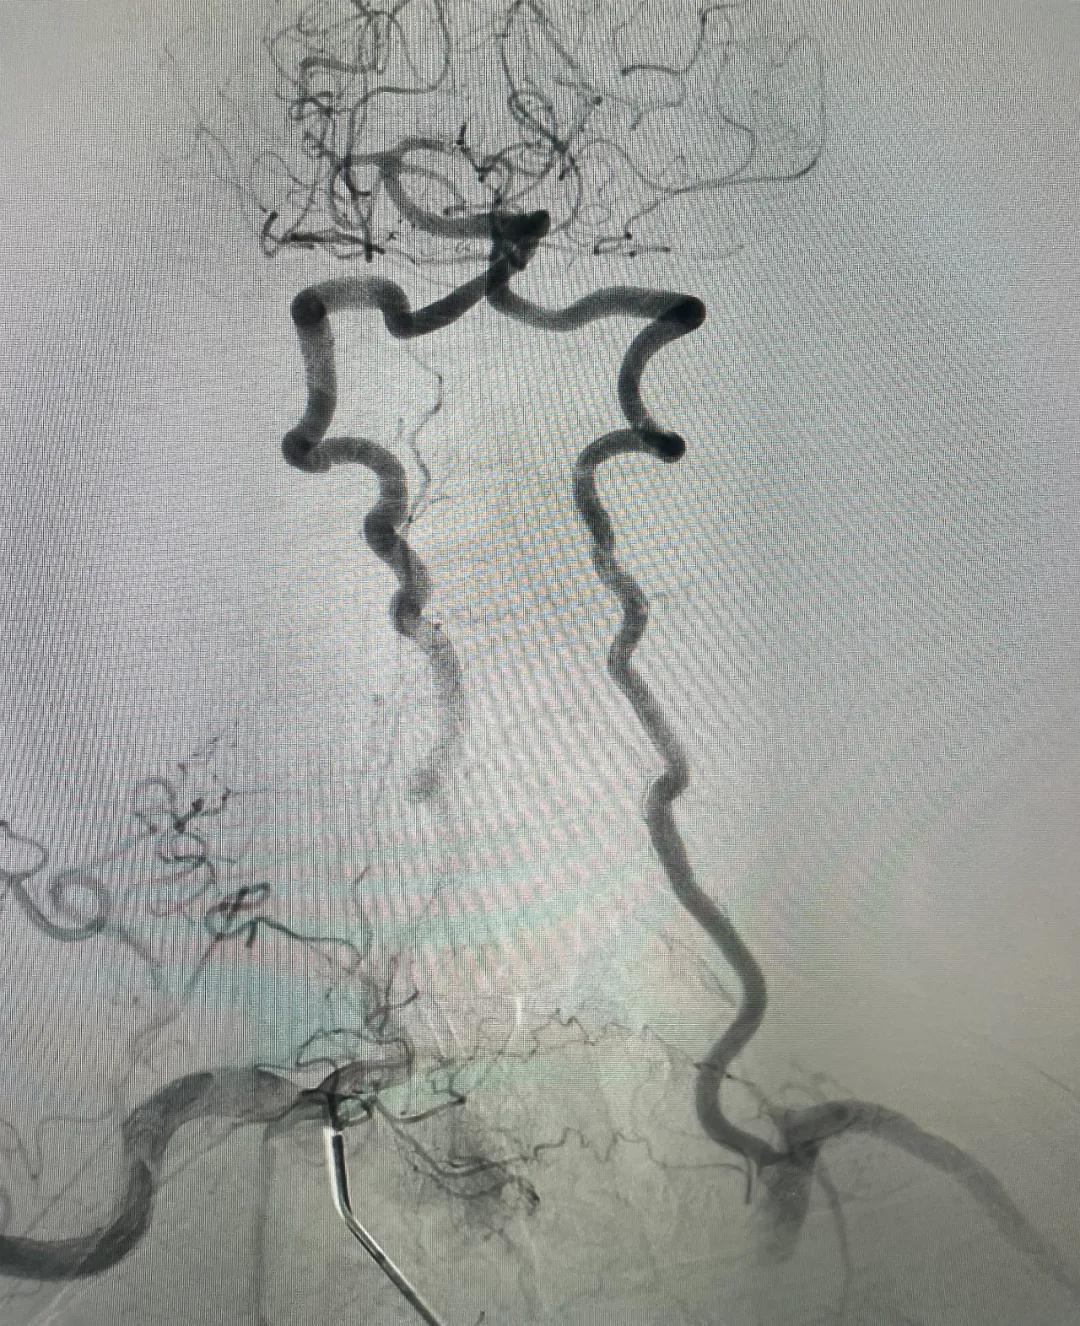

【介入新时代】乌兰察布市中医蒙医综合医院首例全脑血管造影术成功,开启脑血管诊疗新征程

2025年2月8日上午,乌兰察布市中医蒙医综合医院迎来了一个振奋人心的时刻:在多方紧密配合下,首例全脑血管造影术成功实施。手术顺利完成,患者术后情况稳定,这不仅是医院发展的重要里程碑,更为乌兰察布及周边地区百姓的脑血管健康带来了福音。

全脑血管造影术是脑血管疾病诊断的“金标准”,能精准显示脑血管形态和病变,为后续治疗提供关键信息。这次手术成功,展现了医院神经内科团队的专业实力,也体现了多学科协作的高效。

全脑血管造影术:精准锁定脑血管病变,为后续治疗筑牢根基。